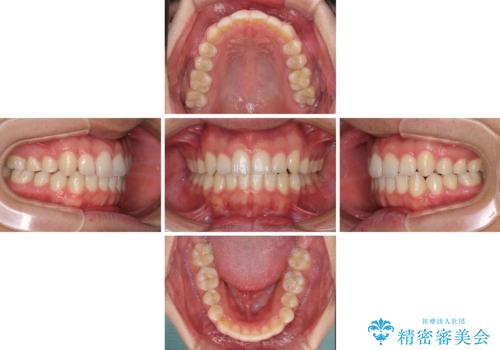

狭い歯列と前歯のデコボコ インビザラインによる矯正治療

- 上下前歯のデコボコを気にして来院された患者様です。

インビザラインによる上下歯列の拡大と、IPR(歯と歯の間を削る)にるスペースの獲得により、前歯のデコボコと狭い歯列を改善することとしました。

比較的軽度な歯列不正であったため、治療期間はそれほど長くはならないと予想されました。

しかしながら、あまりしっかりとマウスピースを装着していなかったため、思いの外期間が長引いてしまいました。

また、仕上がりの歯列にも若干の叢生が残ってしまいました。